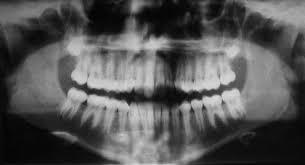

Desarrollo la ortopantomografía, es considerado el padre de la radiografía panorámica